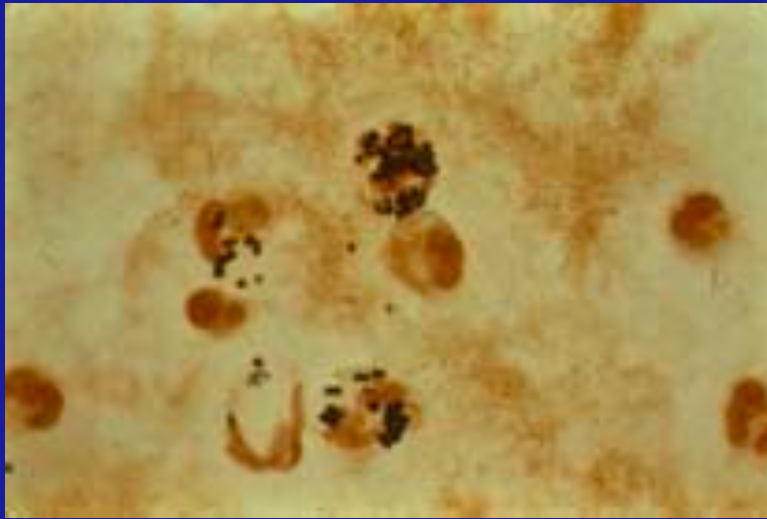

Wright Giemsa stains…

Histoplasma

Leishmania

Trypanosomas

Malaria